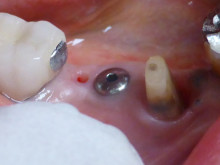

3か月目に 仮のインプラントをとりました。